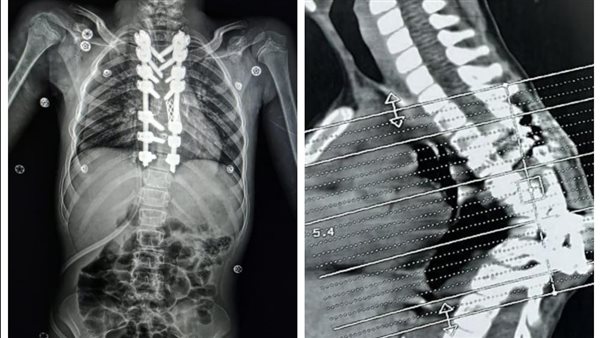

كان مستشفى الإصابات استقبل طفلة تعاني من تحدب شديد وصل إلى 85 درجة نتيجة لدرن فقري سابق، وهو ما كان يهدد حركتها ونموها بشكل طبيعي، وكان التشوه ناتجًا عن درن في العمود الفقري، وقد زاد الأمر تعقيدًا بسبب وجود جراحة سابقة، أجريت لها بإحدى المستشفيات، لتثبيت الفقرات بواسطة مسامير وأعمده وقفص معدني، والتئام كامل للفقرات في وضع معيب، مما أدى إلى حدوث تحدب واعوجاج حاد في الفقرات الظهرية.

كما قام الفريق الطبي باستخدام جهاز مراقبة الأعصاب، وهو تقنية حديثة متقدمة لجراحات العمود الفقري، وتعد الأولى من نوعها بصعيد مصر، لإجراء شق عظمي لفقرتين من الفقرات الظهرية، وضبط وتثبيت الفقرات بمسامير فقرات وأعمدة وقفص كربوني، بالإضافة إلى ذلك، استخدم فريق التخدير تقنيات حديثة وغير تقليدية سمحت بالمراقبة الفسيولوجية اللحظية للأعصاب والعضلات طوال فترة العملية.

وبفضل هذه الجهود المبذولة من الفريق الطبي، تم تصحيح التشوه بنجاح، وخرجت الطفلة من العملية في حالة مستقرة، وعادت إليها الحركة بصورة طبيعية.